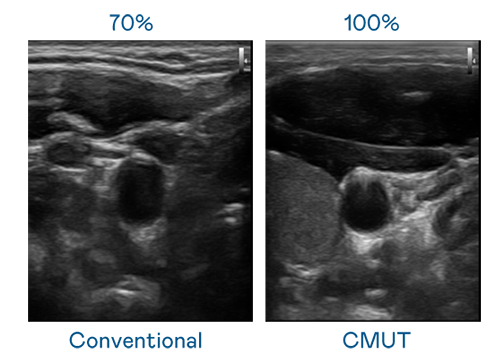

CMUT 技术是一种用电容式微机电元件来产生超音波讯号的技术。与传统 PZT 压电式技术相比,CMUT 频宽增加 30%,更宽频的超音波讯号让影像解析度大幅提升,是实现高影像品质医疗超音波扫描、促进精准医疗发展的关键技术。

超音波影像的解析度高低,首先取决于探头能发出的讯号频宽。九州酷游 CMUT 可提供高清晰的超音波讯号,提供高频宽、高灵敏度、影像纹理细节更高的超音波影像,协助医护人员缩短影像判读时间及利用精准的医疗影像进行诊断。